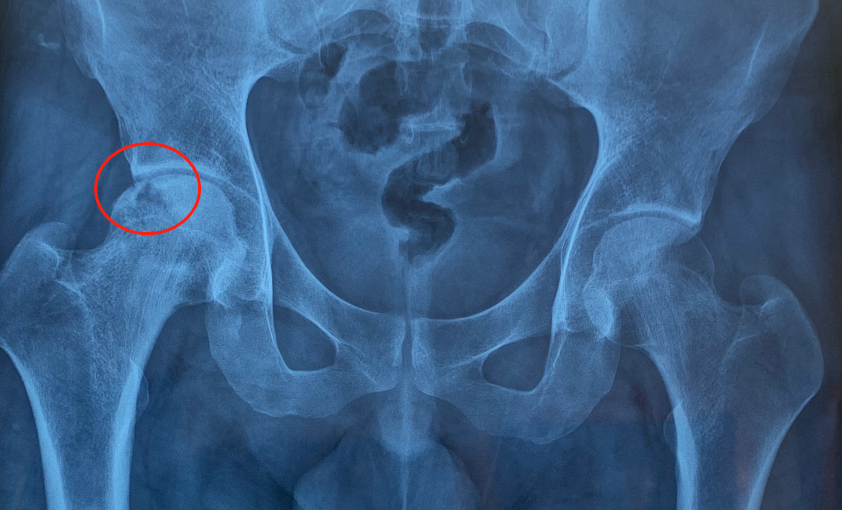

67岁男子确诊股骨头坏死,强忍泪水坦言:髋部疼痛,却未重视【案例】要是早点发现就好了,其实我的髋关节早就出现了问题。一名67岁的刘先生在医院里强忍泪水,语气里带着悔意,他坦言:“髋部疼痛,我一直以为是老毛病,没当回事。”然而再多的后悔也无法改变已经确诊的事实——股骨头坏死。这位刘先生的病情让人唏嘘。股骨头坏死并不是一...

65岁男子确诊股骨头坏死,哽咽诉说:走路早就跛行,却当成小毛病很多人对“股骨头坏死”这五个字充满误解。它并不是突然“断掉”的骨头,而是股骨头内部的骨小梁因为长期供血不足而逐步失去活性,像一... 股骨头形态改变,关节间隙受累,疼痛从“偶尔不舒服”变成“持续影响睡眠”,这时再去就医,选择往往更被动。如何确诊?体格检查能提供方向...

刘欢近况曝光!62岁患“不死癌症”风采依旧,满头银发仍洒脱!自2009年被确诊患有“股骨头缺血性坏死”后,便逐渐淡出公众视野。如今再度现身,他的状态让人惊喜又感慨。 --- 与“不死癌症”抗争十几年 股骨头缺血性坏死,这个听起来晦涩的医学名词,已成为纠缠刘欢十几年的梦魇。 这种疾病为何被称为“不死癌症”? 简单来说,就是股骨头血液...